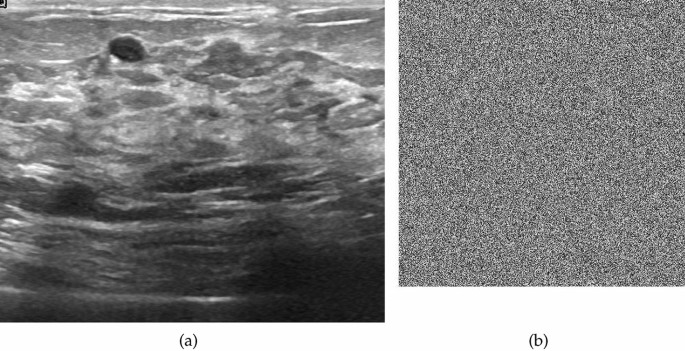

Image encryption

The utilization of the proposed S-box in the realm of encrypting medical images demonstrates a potential avenue for enhancing data security and privacy within healthcare systems. Strong protection against unauthorized access and online threats is required due to the delicate nature of medical images, which frequently contain sensitive patient information. When the innovative S-box is incorporated into encryption techniques, it offers a way to enhance the security of these priceless medical assets. The S-box enables the development of complicated encryption algorithms that thwart adversaries’ attempts to undermine the security of medical images by increasing the non-linearity and confusion aspects of encryption methods. In the constantly changing world of healthcare technology and information security, this novel technique has the potential to significantly protect patient privacy and guarantee the accuracy of medical data. We employed the CBC mode of AES to encrypt plain images with the proposed S-box. The corresponding images are displayed in Figs. 1, 2, 3, 4, 5, 6, 7 and 8. The Fig. 9 depicts the strength against salt and pepper noise with different intensity levels and Table 3 discusses the different tests for an image encryption.

Plain and cipher ultrasound image.

Histogram of plain and cipher ultrasound image.